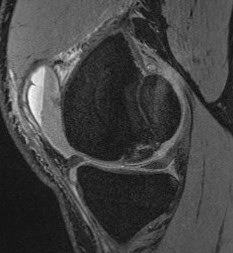

T1 sagittal on presentation T1 sagittal six months later

Stable lesion with no cysts Stable lesion with cysts